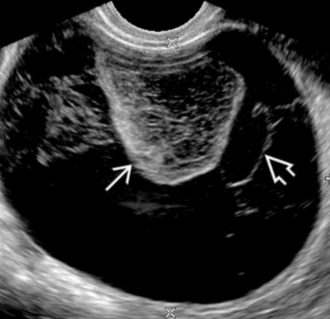

• Has a cobweb appearance - US below

• Retractable clot (left thick arrow in US below)

• No color on doppler